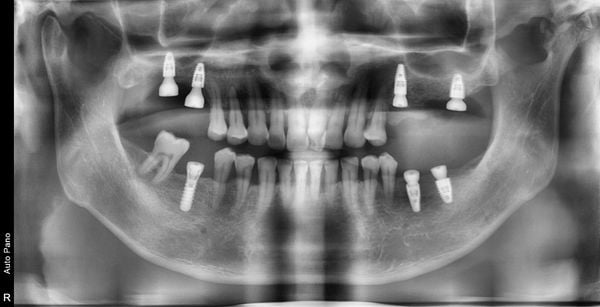

Trồng răng Implant - Nha khoa Á Đông

Hình ảnh chụp X-quang khách hàng đã cấy ghép Implant